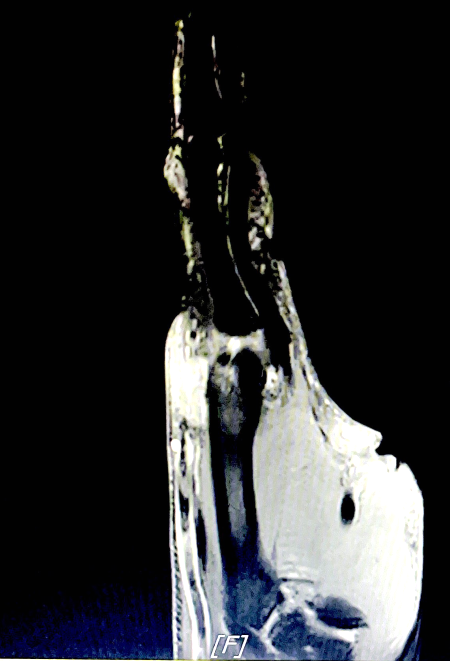

▲核磁下左手第二近端指间关节痛风石图像

在风湿免疫科学科带头人谢悦胜及陈波主任的指导下,医疗团队评估确认该患者符合痛风石清除手术各项指征:无手术禁忌症、痛风性关节炎非急性发作期、关节无红肿疼痛且手术区域皮肤无感染病灶,可有效规避术后感染及痛风急性发作风险,术前还为患者规范使用口服药物进行降尿酸预处理;结合影像科辅助检查结果可见,患者体内痛风石大小约 26mm×17mm,周边邻近骨质已出现吸收与破坏改变,若拖延至关节严重损毁、皮肤破溃流脓后再实施手术,即便完成痛风石清除,受损的关节功能也大概率无法恢复。